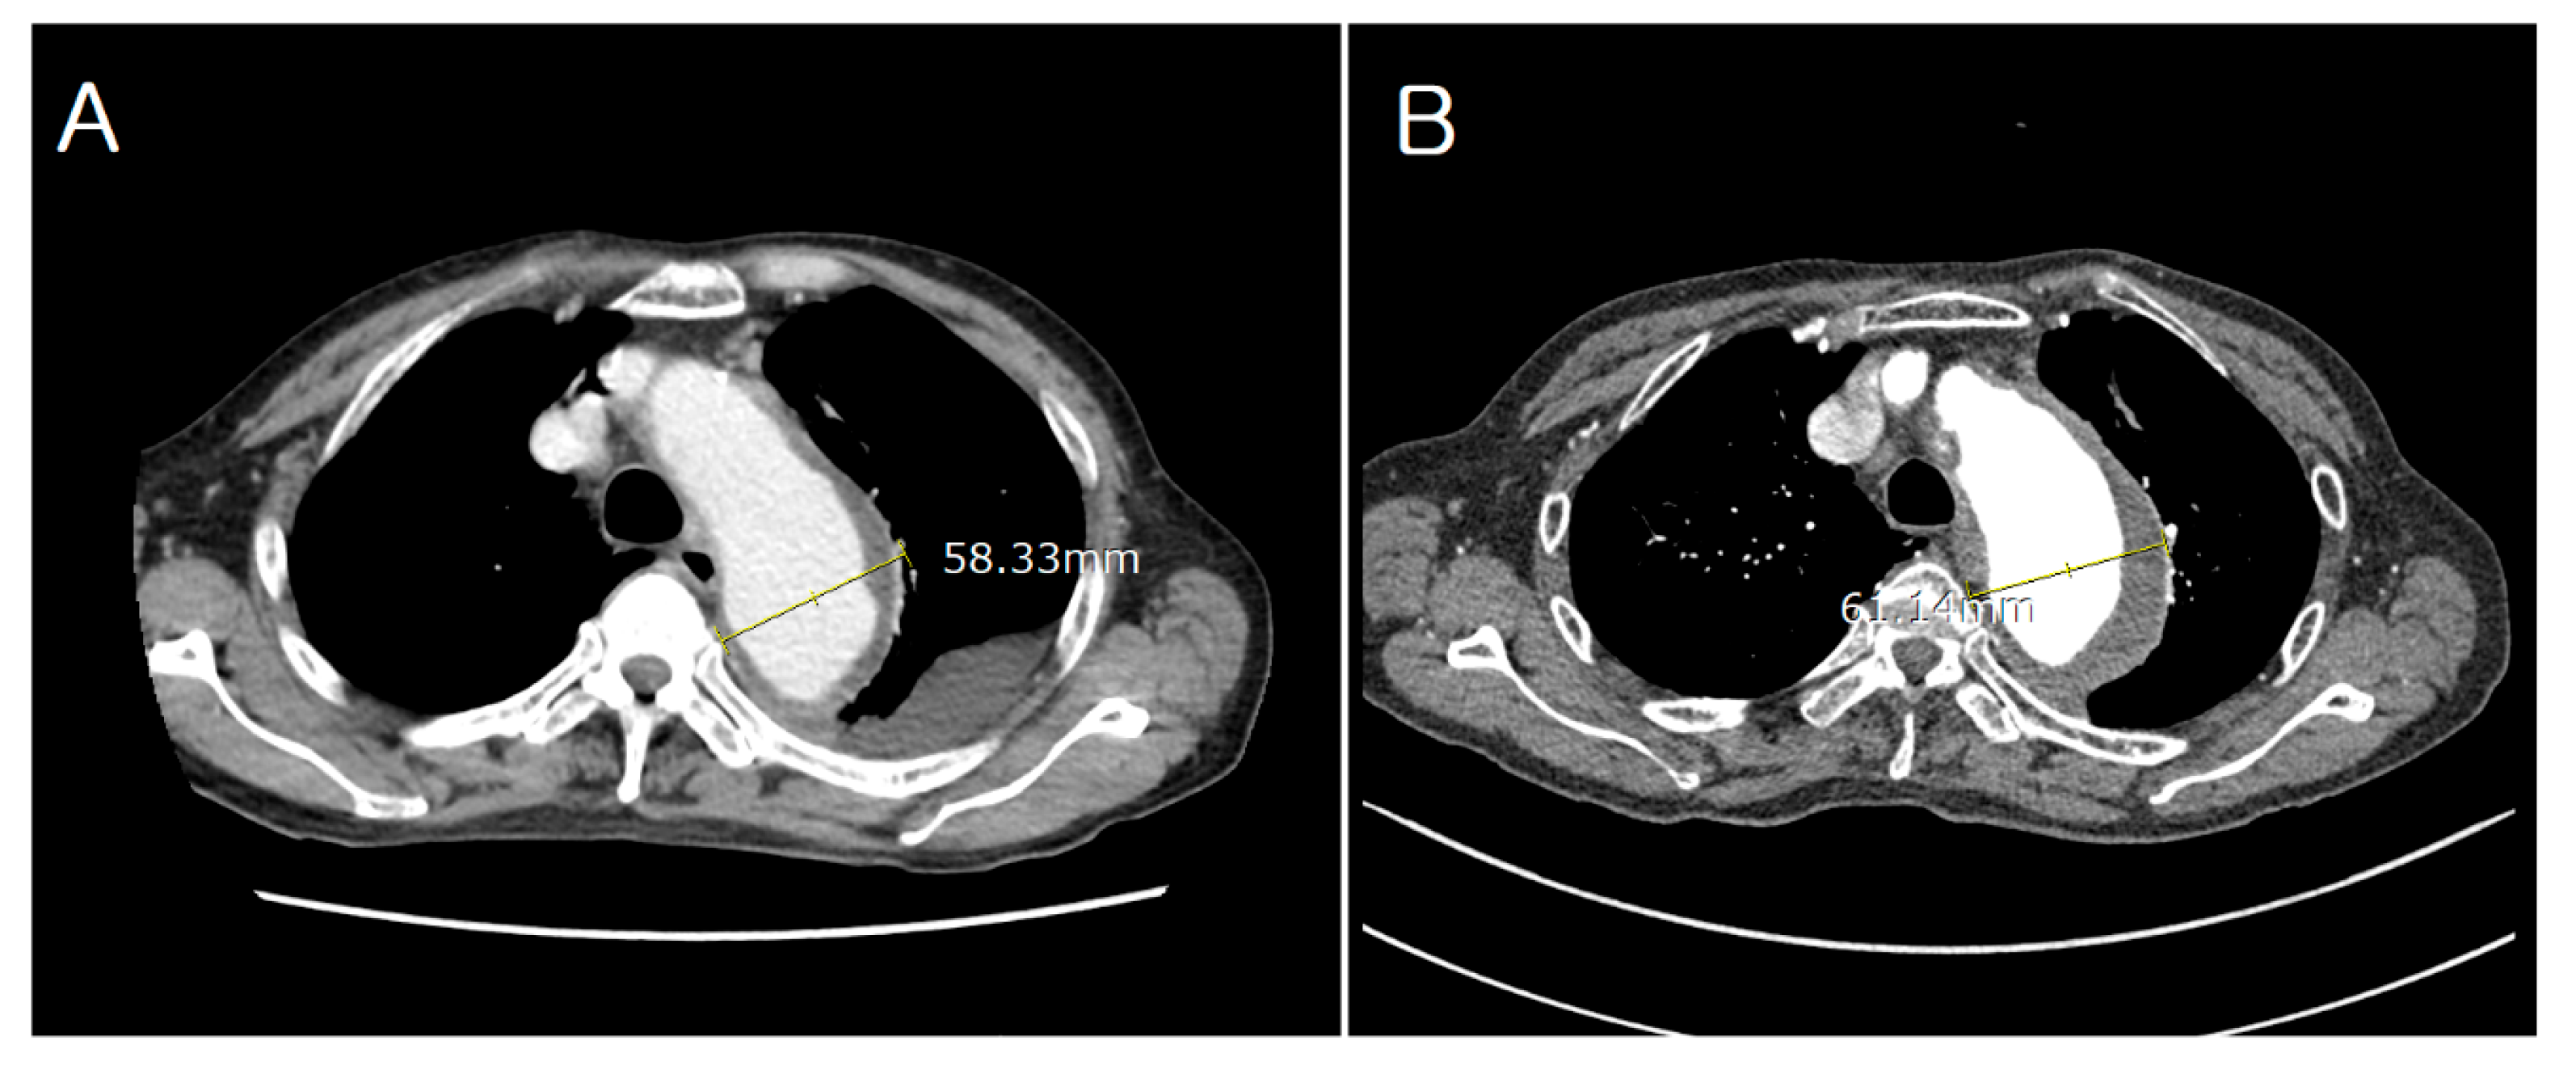

2. Case Description